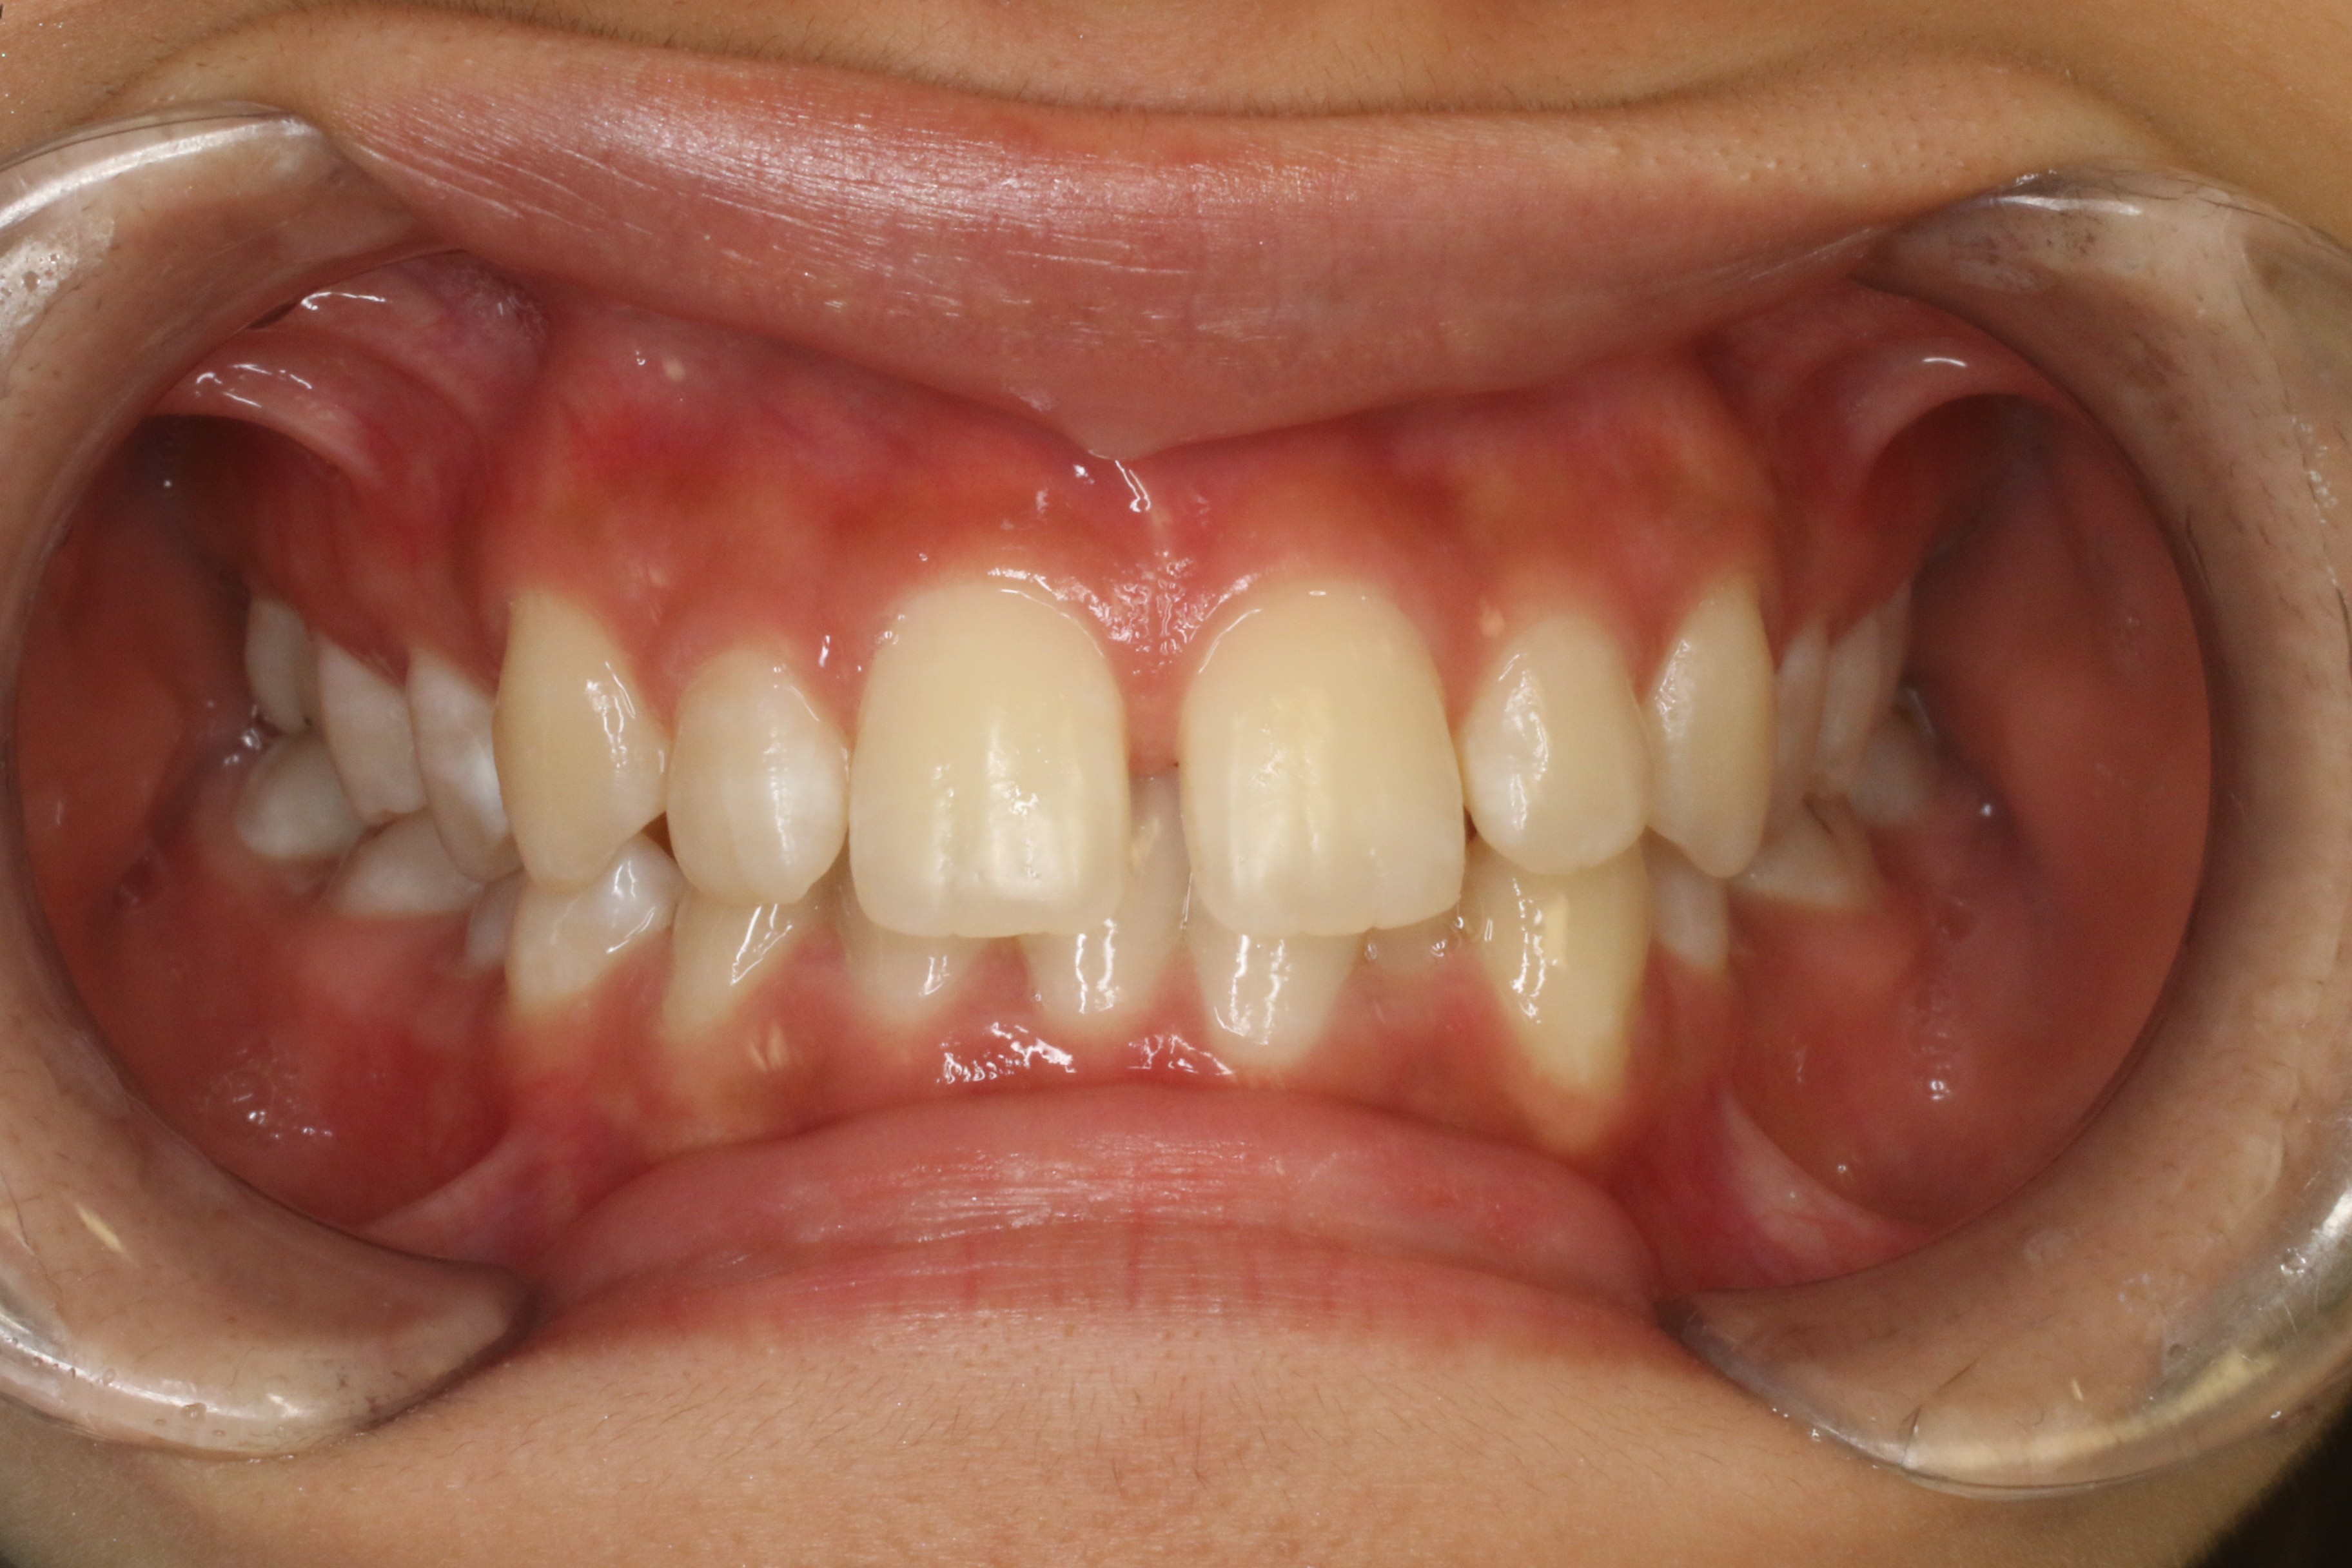

すきっ歯を治したい

年齢層 20代

性別 女性

主訴 【主訴】すきっ歯を治したい 【診断・症状】空隙歯列、1,1正中離開

治療費用 検査・診断:38,500-/裏側矯正治療:1,397,000-(※全て税込)

治療期間 約1年8か月(22回)

抜歯 無(非抜歯)

矯正の装置 裏側矯正(舌側矯正)

副作用、リスク 歯肉退縮,歯根吸収,疼痛,咬合の違和感,装置の違和感,虫歯,歯肉炎

case6_すきっ歯_before

Before

case6_すきっ歯_after

After